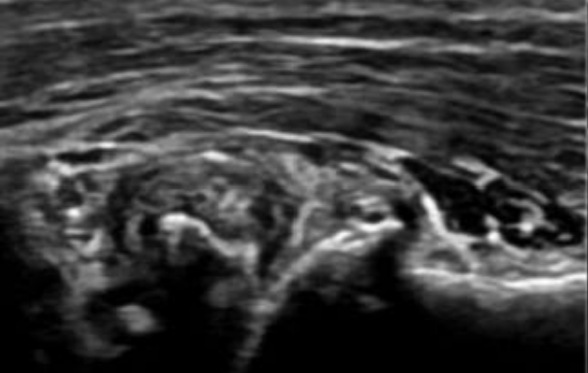

滑膜炎是因为关节内的滑膜受到外伤等刺激因素,产生炎症,造成分泌液失调,形成积液的一种病变,主要表现为关节处的疼痛、肿胀、局部温度升高以及关节活动受限等。滑膜炎主要可分为膝关节滑膜炎、髋关节滑膜炎、踝关节滑膜炎。